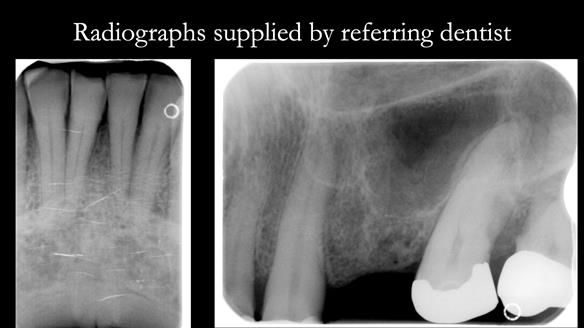

Case Overview: Brian was referred to me for specialist prosthodontics by his general dentist.

- Bruxism: The upper and lower teeth are worn and chipped due to heavy clenching and grinding. With a powerful bite and limited space for replacement teeth, dental implants supported fixed teeth are not recommended. A simpler solution is a metal-based partial denture/splint (“Combat denture”) as planned below. This will act as a splint to protect and replace the missing teeth.

- Restored Teeth: The remaining upper teeth and lower back teeth have large fillings and crowns, making them structurally weak. The new denture will reduce the forces on these teeth to help them last longer, though they may still require new restorations or extractions occasionally.